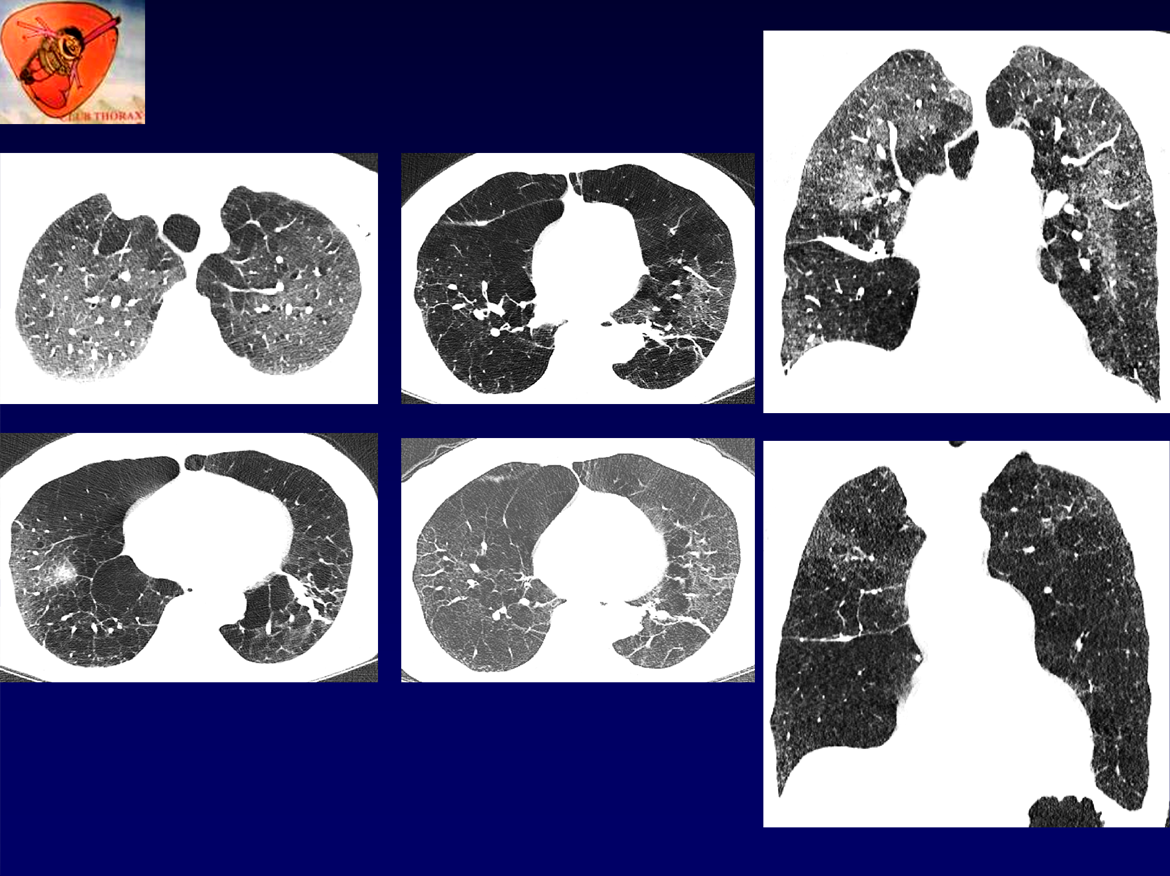

Femme , 76 ans, non tabagique

ATCD: PR traitée depuis 4 ans par du plaquenil, problèmes respiratoires dans l’enfance et dans la famille, asthme depuis 35 ans. Mélanome dorsal opéré à 2 reprises (2022).

Examen: thorax distendu, MV aboli.

RT: hyperclarté , distension, gracilité vasculaire des LI.

EFR:

Tiffeneau = 28%

VEMS 30% (0,5L)

VR 3,5 L (159%)

Désaturation effort++

QUEL EST VOTRE DIAGNOSTIC ?